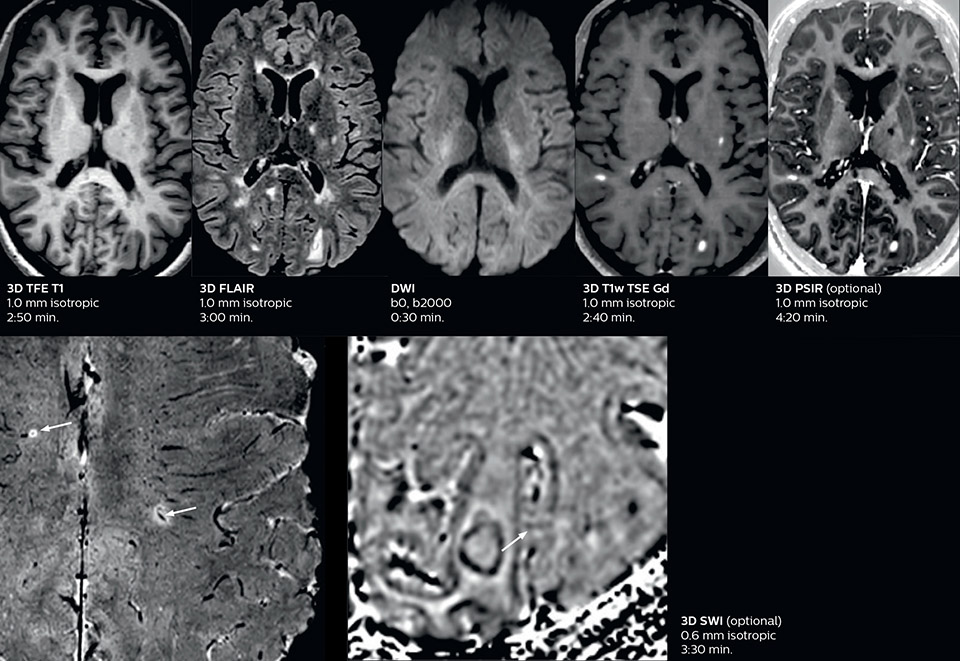

Fast MS protocol with optional sequences

The abbreviated MS protocol for brain is only around 9 minutes, so in case of suspected multiple sclerosis, one or two more advanced sequences may be added, such as PSIR (phase sensitive inversion recovery) or susceptibility-weighted sequences to help us make more confident diagnoses in these inflammatory cases.

In this example, the optional 3D multishot susceptibility weighted sequence with 0.6 mm isotropic voxels is 2 lesions with a central vein sign (arrows) and one lesion with a phase-rim sign (arrowhead). The total scan time, including SmartBrain and axial PD/T2 3mm, is 11:10 min. and is 18:30 min. with the optional 3D PSIR and 3D SWI multishot included.

3D TFE T1

3D FLAIR

DWI image

3D T1w TSE Gd

3D PSIR

3D SWI